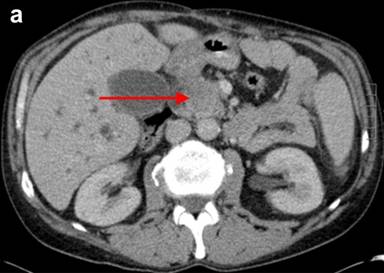

The patient then developed painless obstructive jaundice four months after the procedure. As the clinical features changed and became more sinister, CT scan was repeated, following which a referral was made to the tertiary regional HPB unit. The pre-bypass CT had shown inflammation in the groove with cystic changes in the duodenal wall. A repeat CT at our centre showed a major difference in that there was significant dilatation of the bile duct with a stenosis at the cystic duct insertion site, but the pancreatic duct was not significantly dilated. This was followed by a failed ERCP due to duodenal stenosis hence percutaneous transhepatic cholangiogram and biliary drainage was carried out. MRCP showed a small non enhancing area of low T1 signal within the pancreatic head surrounding the intra-pancreatic common bile duct extending to the ampulla of uncertain significance. CT and MRI scans revealed deleted a soft tissue mass in the head of the pancreas, abutting his superior mesenteric vein (Figures 1 and 2).

|

Figure 1. Pre-operative abdominal CT. a. Transverse CT with arrow indicating the soft tissue mass in head of pancreas and dilatation of the intra and extrahepatic biliary tree. b. Coronal CT with arrow illustrating deleted cystic changes of duodenal wall and intra and extra hepatic dilatation. |